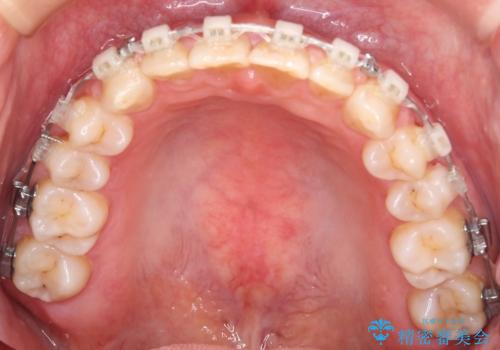

- 矯正装置

- 審美装置

- 前歯のすきっ歯が気になるということで来院されました。今回は抜歯はしないためワイヤー矯正かインビザライン矯正のどちらでも治療可能でしたが、患者さまのご希望により表のワイヤー装置にて治療をおこないました。

前歯に隙間がいくつかあったため、今回は上下でゴムかけを行いスペースを埋めるための力をかけて閉じました。もう少し早く終了する予定でしたが、ブラッシング不良による歯肉腫脹があり、一部スペースクローズに時間がかかりました。